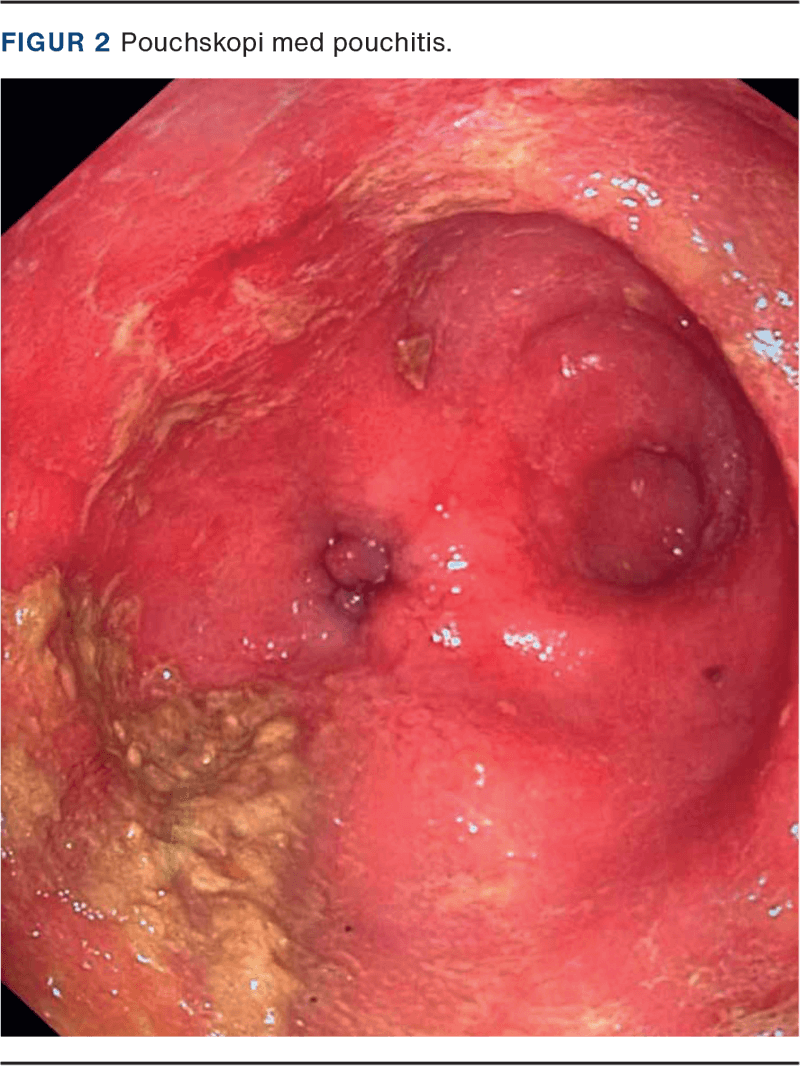

Den væsentligste undersøgelse for at kunne differentiere mellem de symptomudløsende årsager er pouchskopi med biopsi [11]. Denne undersøgelse foretages bedst med fleksibelt endoskop og kan udføres uden sedation. Det er væsentligt at undersøge analkanal, pouch og tilførende tyndtarmsben. Endoskopisk ligner pouchitis kolorektal inflammation ved CU, men det opstår i den ileale pouch [3]. Der findes kun inflammation i selve pouchen og ingen inflammation i hverken cuff eller det tilførende tyndtarmsben. Hos patienter med recidiverende pouchitis, som præsenterer sig med typiske symptomer, er det ikke nødvendigt at udføre fornyet pouchskopi, medmindre der er behandlingssvigt. Histopatologisk undersøgelse af biopsier ved pouchitis vil oftest vise akut og kronisk inflammation. Såfremt man mistænker CMV-infektion, skal dette anføres på patologirekvisitionen af biopsierne (Figur 2).

I meget sjældne tilfælde kan de inflammatoriske forandringer være forårsaget af iskæmi, der typisk viser sig som asymmetrisk inflammation af pouchen [15]. Inflammatoriske polypper kan medvirke til vedvarende symptomer ved pouchitis og bør derfor fjernes i forbindelse med pouchskopien [9].